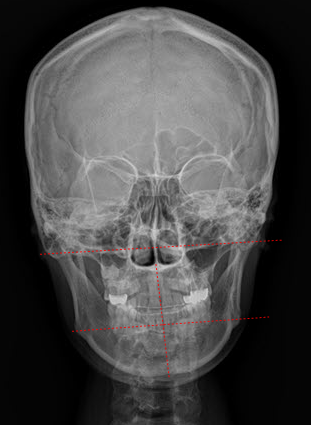

엑스레이(선).png

위의 사진의 환자분의 경우도 입꼬리 비대칭을 주소증으로 오셨는데, 하악과 상악이 반대반향으로 돌아가면서 한쪽으로 찌그러진 안모를 갖고 있습니다. 입꼬리가 왼쪽으로 끌려올라가 있을 뿐 아니라 좌우 광대 위치도 다르고 상대적으로 왼쪽 볼꺼짐도 심한 상태로 얼굴의 좌우 불균형이 상당히 깨진 안면비대칭입니다. 오른쪽 엑스레이 상으로도 틀어진 안모가 한 눈에 보입니다.